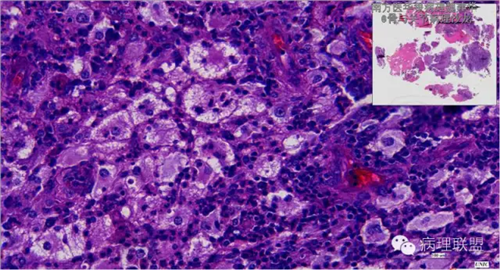

来源于组织细胞的相似性骨病ECD vs RDD 看图说话